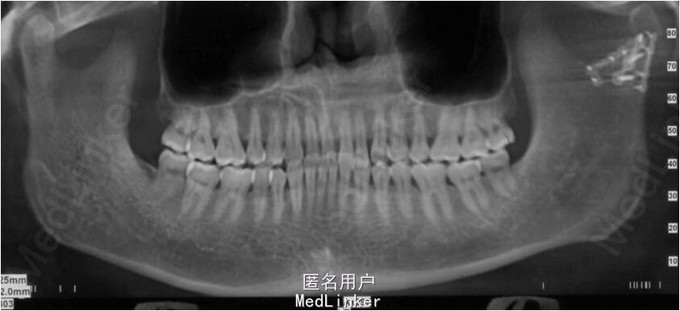

颏部可见擦伤,其余部位未见明显外伤。曲面断层和CT提示,左侧髁突骨质连续性中断

术后髁突愈合良好